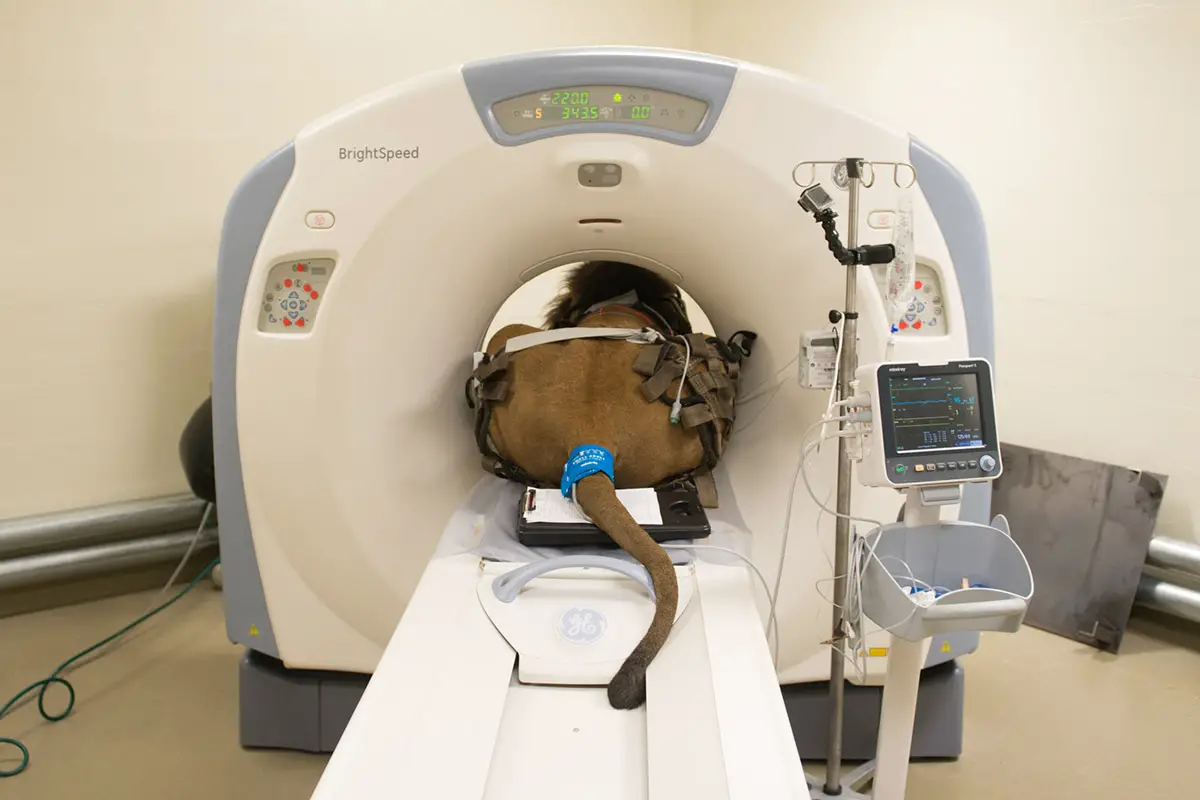

Just A Routine CAT Scan : R/funny

www.reddit.com

www.reddit.com

scan cat funny routine just ct cats lion big